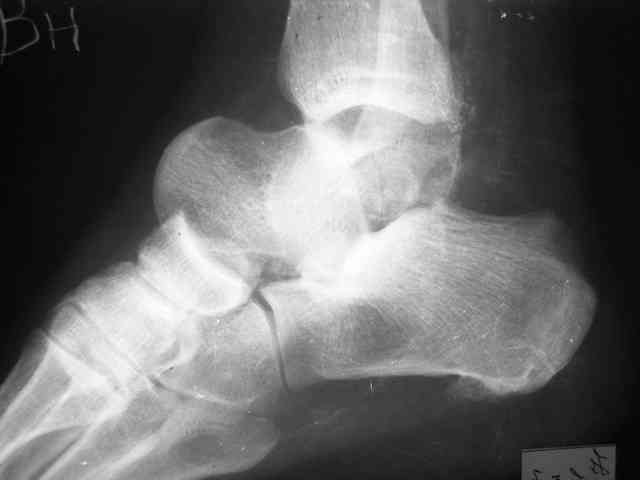

Re: Редкое повреждение - полный вывих тарана!

Уважаемый Александр! Как обещал представляю Р-граммы и операционные фото.